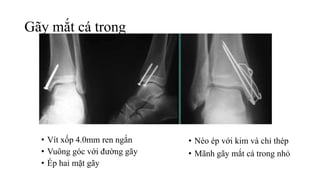

Gãy mắt cá trong

• Vít xốp 4.0mm ren ngắn

• Vuông góc với đường gãy

• Ép hai mặt gãy

• Néo ép với kim và chỉ thép

• Mãnh gãy mắt cá trong nhỏ